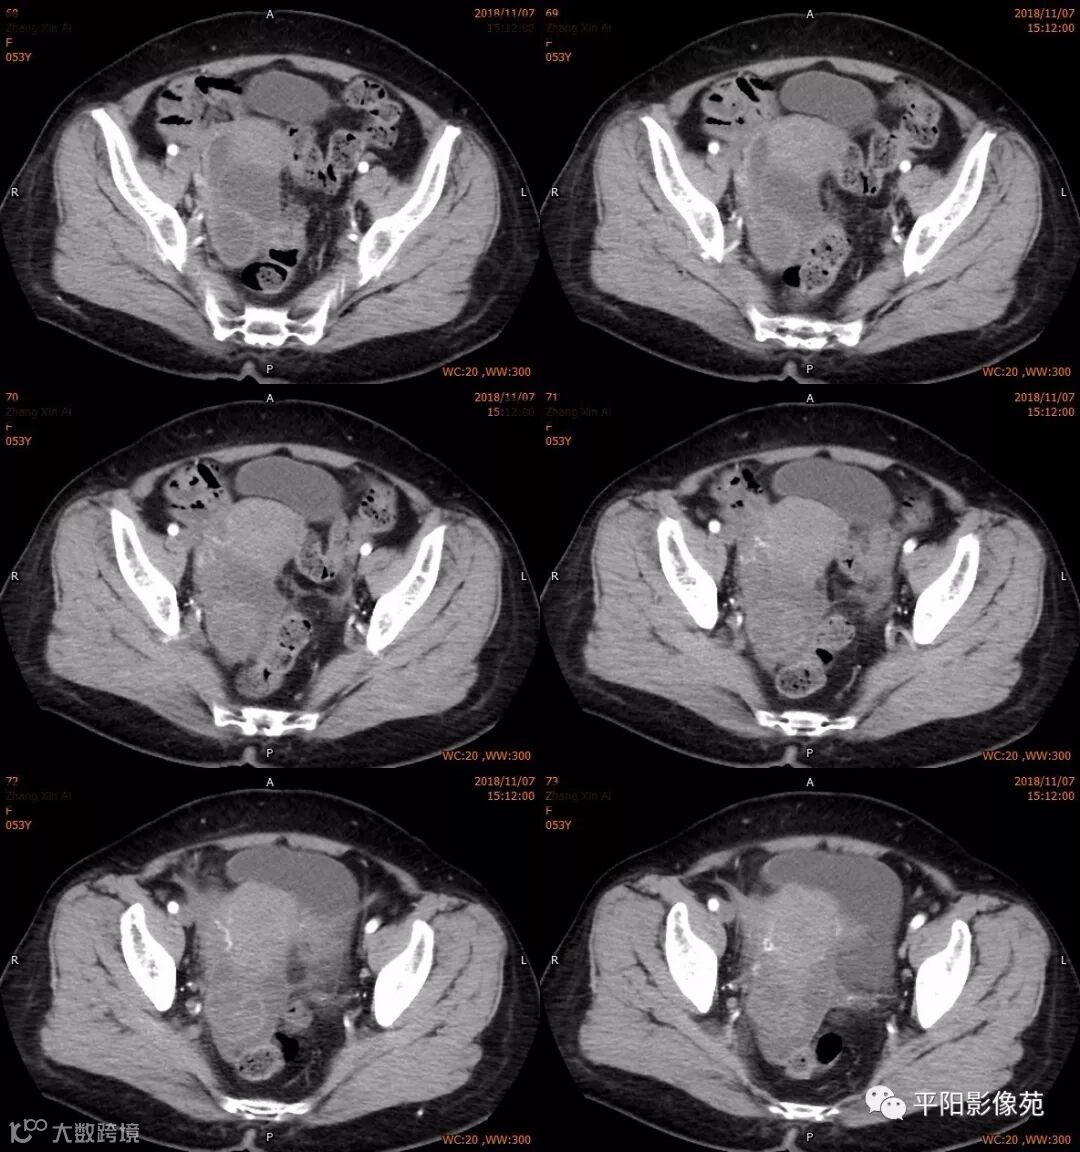

右附件区薄壁囊性病变,壁明显强化,边界不清,供血动脉源自子宫动脉,且局部动脉血管增多;其内侧可见卵圆形无强化囊性病灶。

附件区病变多见于卵巢,以囊性为主的病灶多为卵巢囊肿、粘液/浆液性囊腺瘤、皮样囊肿等,这些病灶都具有鲜明瘤体结构,且壁强化多为轻-中度,供血动脉多源自卵巢动脉;而本例患者右附件区薄壁囊性病灶,多位置观察形态为迂曲管状,且壁有明显延迟强化,供血动脉源自子宫动脉,较对侧血管丰富,故而考虑源自输卵管或子宫病变,但子宫发生的薄壁囊性病变较少,多见于子宫肌瘤囊变,完全囊变者少见,且形态轮廓与肌瘤相同为球形故而排除,结合患者腹痛前有感冒病史,且有压痛,因此考虑输卵管积脓可能。其内侧无强化囊性肿块,考虑卵巢囊肿可能。